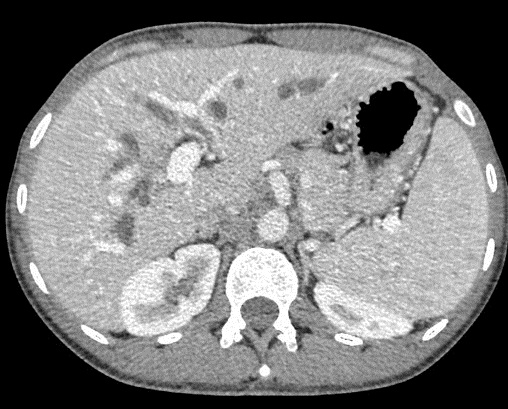

Image radiologique d'une CSP en

coupe TDM axiale avec de conrtrast

intraveineuse . Aspect de dilatation et

stricture stenosant systematise des voies

biliaires intrahepatique . Foie

elargir et splenomegalie |

|